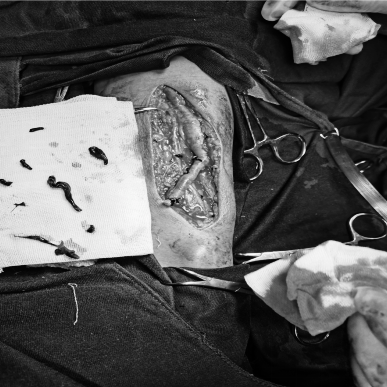

5月28日,贵州航天医院第63次晨读会由我院肾脏风湿科副主任医师李玫作学术交流,她以“类风湿关节炎的诊疗进展”为题,系统讲解了类风湿关节炎的发病机制、临床表现、实验室辅助检查、治疗方案及预后管理,重点围绕疾病诊断标准与治疗策略展开论述。在治疗领域,分别从传统药物治疗路径、生物靶向治疗新进展及外科干预时机三个维度进行阐释,并结合临床实践对治疗方案的选择原则作出说明。 肾脏风湿科专家简介 冯远军 中共党员,肾脏风湿、肝胆外科党支部书记,肾脏风湿科主任,主任医师 临床擅长:对慢性肾脏病、急性肾损伤、急慢性肾小球肾炎、肾病综合症、风湿性疾病、间质性肾炎、肾小管损伤等疾病的诊治及血液透析技术、动静脉内瘘成形术及疑难病例的诊治具有丰富的临床经验。 曾在上海市第一人民医院及贵阳市第一人民医院进修学习,贵州省医学会肾脏病学分会第五届委员会委员,遵义市医学会肾脏病学分会第一届委员会副主任委员,遵义市医学会风湿病学分会第一届委员会副主任委员,荣获“贵州航天劳动模范、遵义市汇川区先进工作者”,遵义市医疗事故鉴定专家库成员,主持省市级科研项目4项,完成4项,近5年发表论文10余篇,北大核心期刊1篇。 王卫华 肾脏风湿科主任医师 临床擅长:从事临床工作28年,擅长尿毒症患者血管通路的建设及维护(如标准和高位动静脉内瘘术、取栓+内瘘重建术、内瘘狭窄球囊扩张术、长期中心静脉置管术及肾穿刺活检术)等手术,对原发性和继发性肾病综合征、急、慢性肾小球肾炎、慢性肾脏病、泌尿系感染、结缔组织病、急性中毒、痛风、贫血、血小板减少症等疾病诊治及血液透析技术应用等具有丰富的临床经验。 1995年毕业于遵义医学院临床医学系,曾前往重庆医科大学进修学习肾脏疾病及血液净化;遵义市医学会肾脏病学分会常务委员,遵义市血液净化质量控制中心委员;先后发表肾病专业省部级医学刊物医学论文8篇,主持市级科研项目2项。 李丽华 中共党员,肾脏风湿科副主任医师 临床擅长:从事临床工作17年,对慢性肾脏病、急性肾损伤、急慢性肾小球肾炎、肾病综合征、风湿性疾病、间质性肾炎、肾小管损伤、急慢性肾衰竭的血液透析、CRRT治疗以及血管通路的建设维护等具有丰富的临床诊疗经验。 2006年毕业于遵义医学院临床专业,曾在遵义医学院附属医院完成住院医生规范化培养,并前往第三军医大学新桥医院、珠海市人民医院进修学习;中华医学会遵义市肾脏病学分会委员,遵义中医药学会肾病专业委员会委员,遵义市血液净化质量控制中心委员,遵义市医学会血液学分会委员会委员;发表省部级医学刊物医学论文4篇,主持参与省级科研课题1项,主持参与市级科研课题1项,院级新技术6项,获得本专业授权实用新型专利3项。 李 玫 中共党员,肾脏风湿科副主任医师 临床擅长:从事临床工作15年,对慢性肾脏病、急性肾损伤、急慢性肾小球肾炎、肾病综合征、风湿性疾病、间质性肾炎、肾小管损伤等疾病的诊治具有丰富的临床经验,擅长血液透析技术、动静脉内瘘成形术等。 2008年毕业于遵义医学院临床医学系,曾前往遵义医学院附属医院进修学习肾脏病与血液净化相关技术;遵义市医学会肾脏病学分会委员,发表肾病专业省部级医学刊物医学论文4篇。 肾脏风湿科简介 基本情况 贵州航天医院肾脏风湿科2017年建立,住院患者承载能力达到50人左右,透析治疗服务惠及250余人的患者群体,在学科建设、高端医疗设备引进及专业技术队伍已达到区域内领先水平。科室共有医护人员46名,副高级以上专家7名,亚专业设置齐全,涵盖肾脏疾病、风湿免疫疾病药物治疗、透析治疗及透析通路维护等多个专业领域,为患者提供全面、精准、高效的诊疗服务。配备了尖端的医疗设备与智能化的辅助系统,包括透析机、CRRT机等设备。 专科特色 (一)肾脏病治疗领域:专精于血液透析、血液透析滤过、血液灌流、血浆置换、CRRT等尖端技术,致力于为患者量身打造个性化的肾脏替代治疗方案。 (二)在风湿病治疗方面:凭借生物制剂、免疫抑制剂等前沿药物,结合患者的具体情况,精心策划个体化的治疗策略,有效减轻患者症状,显著提升生活质量。 超声引导下球囊扩张术:内瘘狭窄是内瘘最常见的并发症之一,我们采用先进的超声引导下球囊扩张术,通过微创方式恢复内瘘通畅,有效避免了传统手术带来的创伤和痛苦。 内瘘血栓溶栓治疗、取栓术:血栓形成是内瘘功能丧失的主要原因之一,根据患者具体情况,采用溶栓治疗、取栓术等多种手段,确保患者及时恢复透析治疗。 内瘘动脉瘤形成治疗:动脉瘤是由于内瘘局部血流动力学改变引起的血管扩张性疾病,采取佩戴弹力绷带、手术修复等措施,防止动脉瘤进一步发展和破裂。 内瘘感染治疗:内瘘感染是内瘘并发症中最为严重的类型之一,一般采用敏感抗生素进行抗感染治疗,严重者采取手术清创等措施。 内瘘窃血综合征治疗:是由于内瘘建立后,远端肢体血流减少引起的一系列症状,通过调整透析方案、改善内瘘血流分布及必要时重建内瘘等措施,有效缓解患者的症状并提高其生活质量。 诊疗范围 擅长治疗急慢性肾炎、肾病综合征、肾衰竭等肾脏疾病;擅长治疗类风湿关节炎、系统性红斑狼疮、干燥综合征等风湿免疫性疾病,并为患者提供健康教育与康复指导,帮助患者更好地管理疾病,提高生活质量。 end